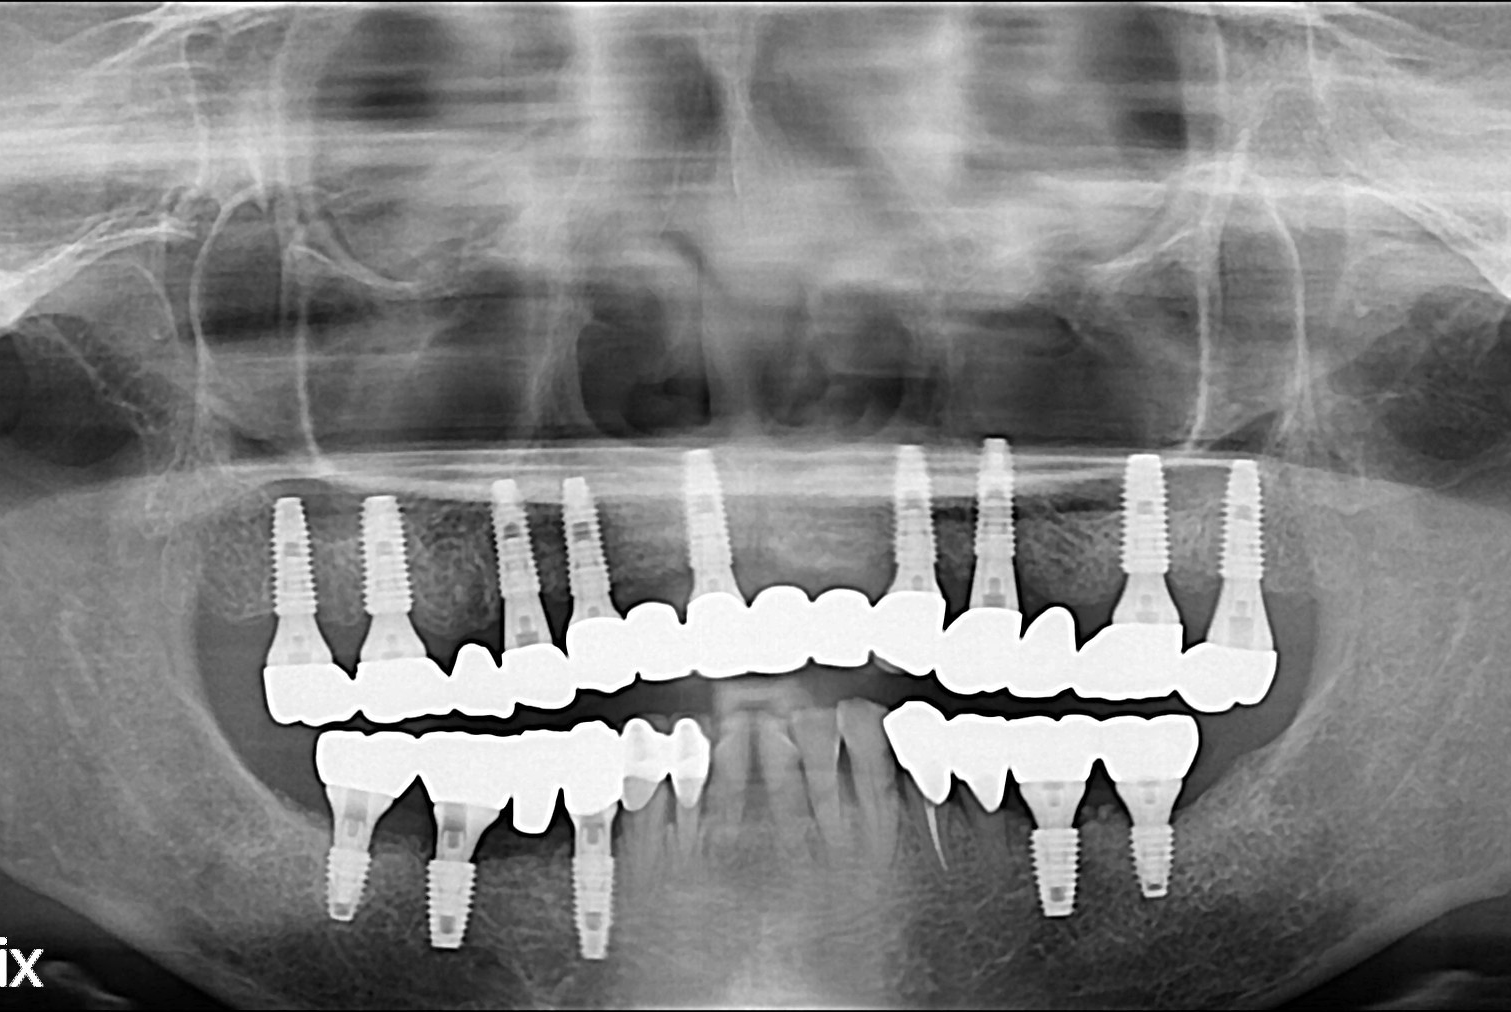

치료후 : 2016-03-30

세종치과는 많은 환자와 다양한 케이스를 바탕으로 항상 편안한 임플란트 수술을 제공하고자 노력하고,

오래동안 튼튼히 쓸 수 있는 임플란트 수술을 가장 큰 목표로 삼고 있습니다